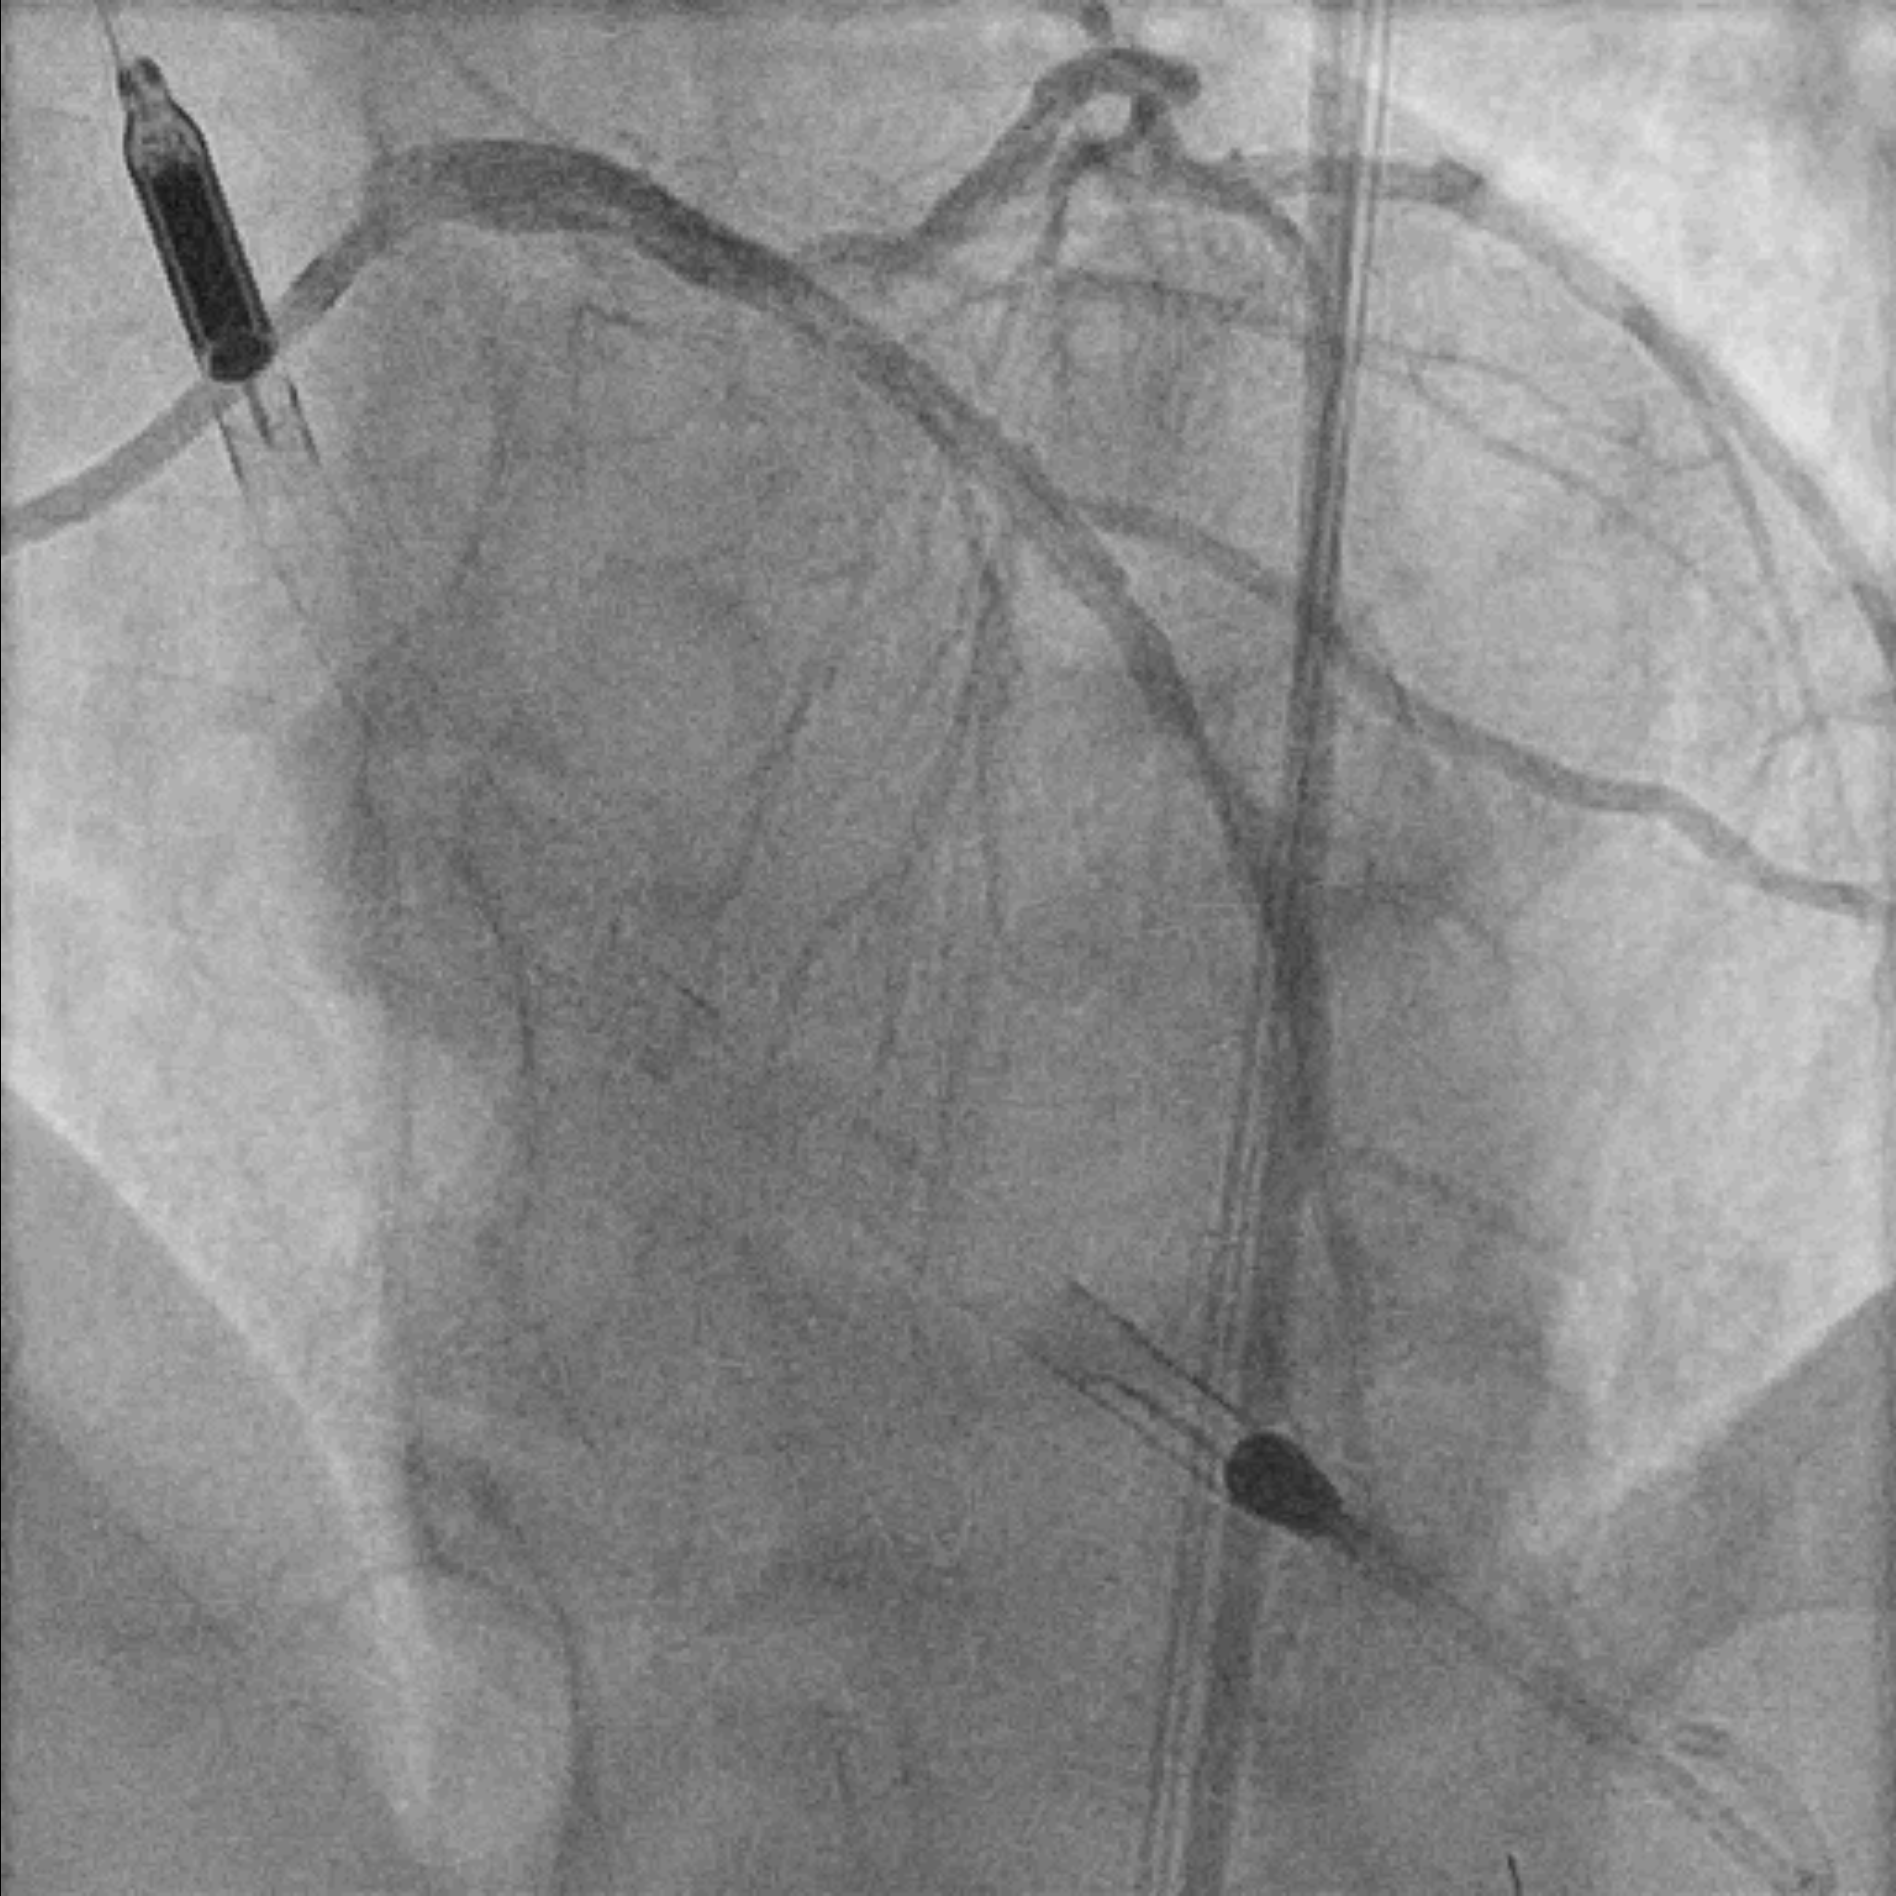

Patient was immediately brought to the catheterization laboratory. During transfer he required escalating inotropic support. LVEDP using a 5Fr pigtail catheter measured 30 mmHg. Coronary angiogram revealed minor disease in LMCA, proximal LAD acute total occlusion, LCx minor disease, proximal RCA total occlusion with no obvious collateral supply.

Left common femoral artery and vein, and right common femoral artery were punctured under ultrasound and fluoroscopy guidance with micropuncture set. Prior to coronary angiogram, Impella was inserted via right common femoral artery into LV. ICU was informed to provide potential ECMO support in the event of further hemodynamic collapse.

EBU 3.5 7Fr was used to engage left main common artery. Proximal LAD lesion was crossed with a Corsair Pro XS supported Fielder XT-R. Dottering with Sapphire 2.0/15 was unable to achieve flow in LAD. Low pressure inflation of 2.0 mm x 15 mm semi-compliant balloon at ostial to proximal LAD restored TIMI II flow. IVUS demonstrated organised clot in pLAD and plaque extension into LM. A 3.5 mm x 48 mm DES was deployed over mid-LM to mLAD at nominal pressure. The stent was further optimized with 5.0 mm x 6 mm and 4.0 mm x 15 mm non-compliant balloons under IVUS guidance. Intracoronary Adenosine was administered to improve coronary flow. Final angiogram showed TIMI III flow with no immediate complications. Faint retrograde flow to distal RCA was observed. A brief attempt to open RCA was made as the chronicity of the lesion was uncertain. However, Fielder XT-A supported by Corsair Pro XS failed to cross the lesion and the procedure was aborted.